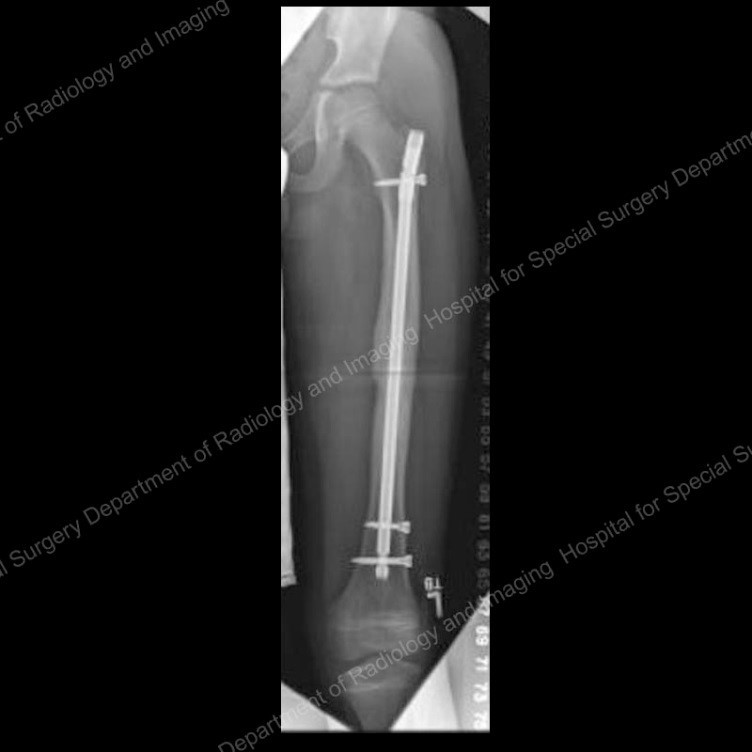

What this ting?

Thomas’ splint